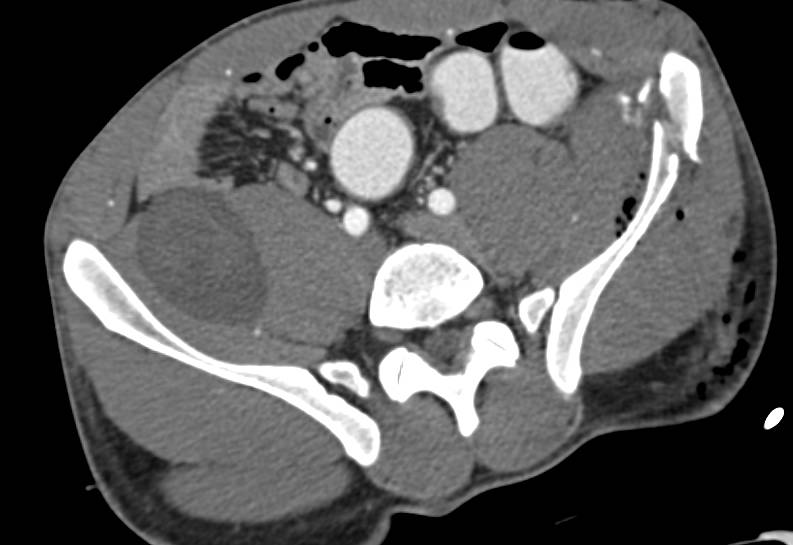

Diagnosis

Ulnar Fracture